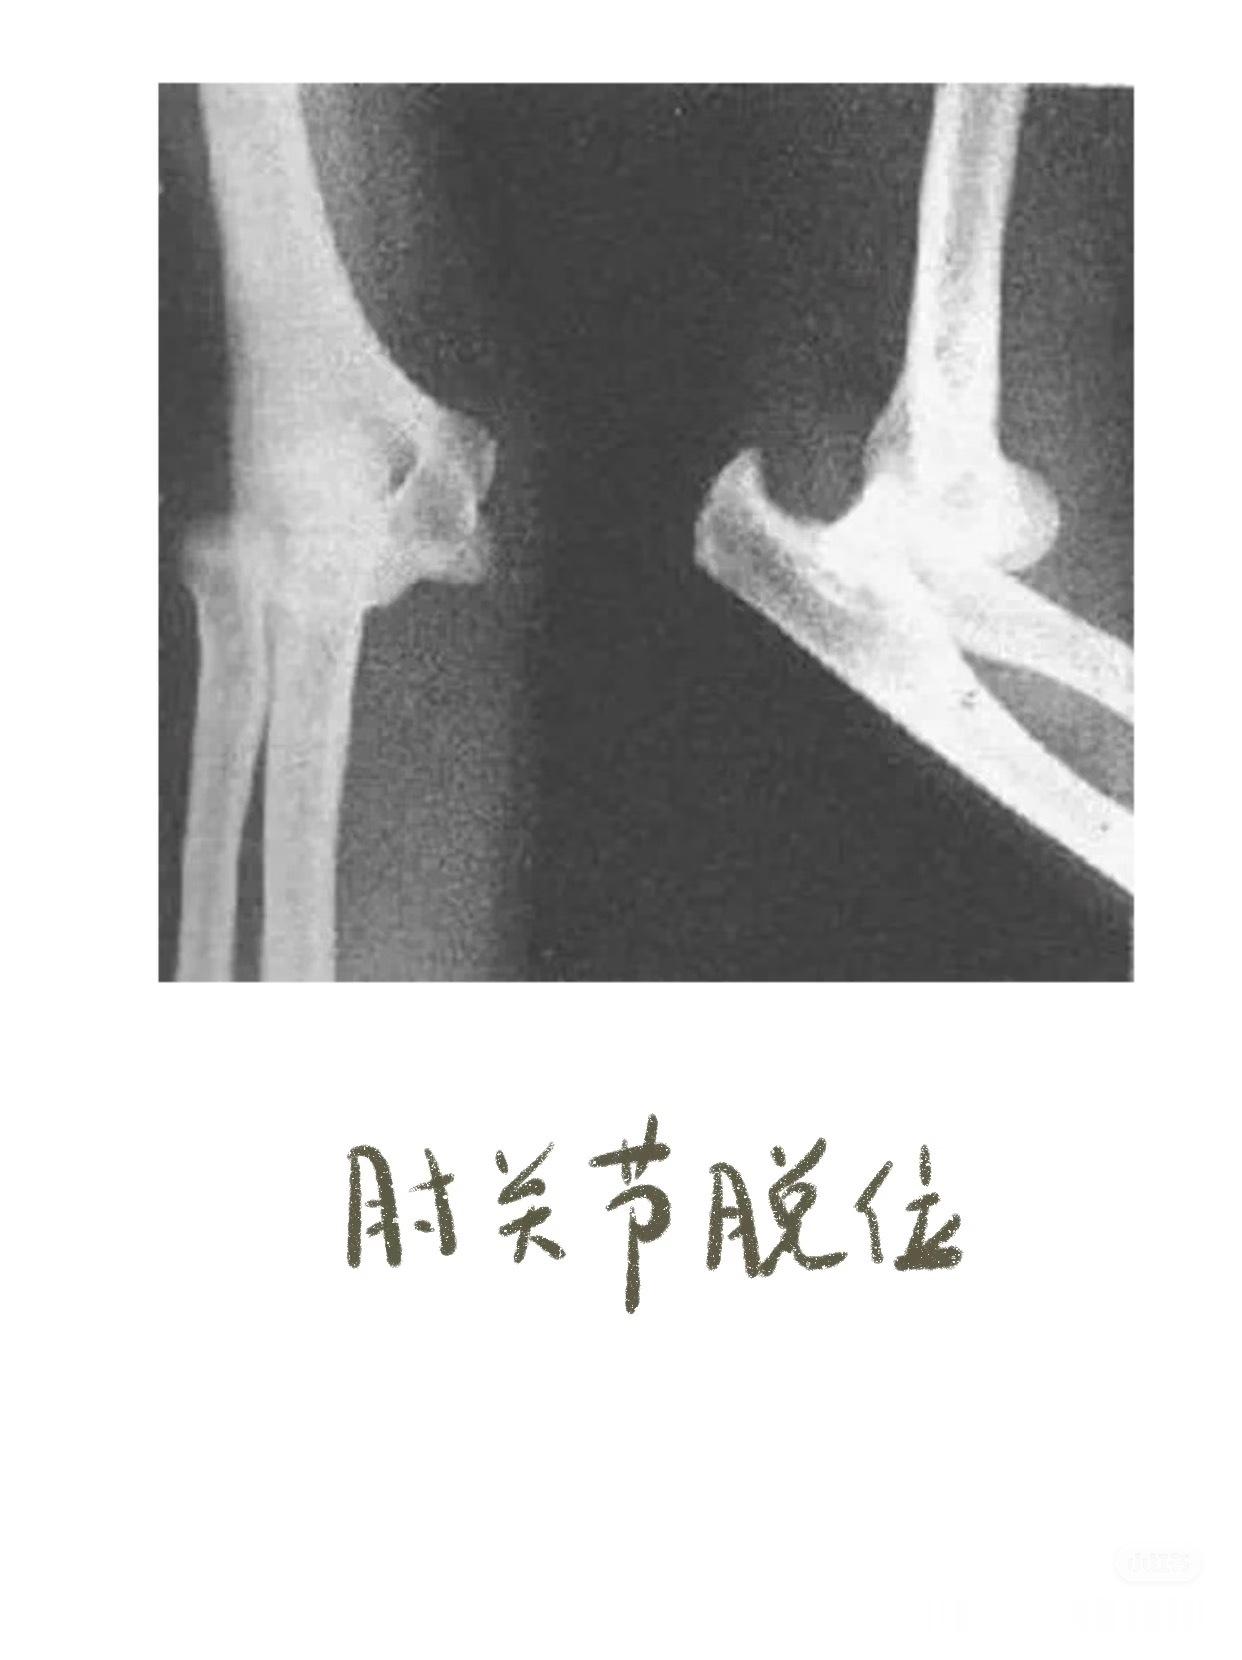

之前讲到影像学片子,膝盖和腰椎比较多,今天说些比较小众的——锁骨骨折,肘关节脱位,手部损伤等等👇🏻👇🏻【锁骨骨折的典型症状】01.疼痛与压痛——骨折部位出现持续性或阵发性剧烈疼痛。02.肿胀与皮下瘀斑——骨折后局部软组织损伤和出血,导致肿胀迅速出现,可能伴随皮下瘀血或青紫。03.畸形与异常活动——锁骨缩短、成角或旋转畸形,如骨折端上翘、隆起或凹陷。04. 活动受限——上肢抬举、伸展等功能受限,肩关节活动时疼痛加剧,甚至完全无法活动。05. 骨擦音/骨擦感——骨折断端摩擦时可触及异常活动或听到骨擦音,是骨折的典型体征。【肘关节脱位】01. 关节畸形——后脱位(最常见):尺骨鹰嘴向后突出,肘前窝饱满,前臂外观缩短,呈“靴状畸形”。——侧方脱位:肘关节向内或向外偏斜,形成肘内/外翻畸形。02. 肘后三角关系破坏 ——正常肘关节屈曲时,肱骨内/外上髁与尺骨鹰嘴构成等腰三角形;伸直时三点成一直线。——脱位后此关系完全失常。03. 弹性固定 ——关节被周围紧张韧带“锁扣”于半屈位,被动活动时有弹簧样阻力感。04. 骨性标志异常 ——后脱位时可触及肘后空虚感,尺骨鹰嘴异常隆起;——前脱位可触及肱骨远端。【手部骨折】拳击手骨折——握拳撞击——通常发生在第五掌骨(cr.骨科小龙笔记)大家如果还有关于骨折或者其他身体损伤的问题,都可以下方留言讨论